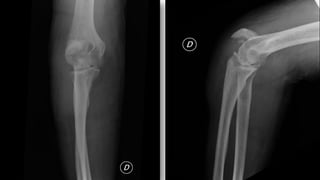

FRACTURA CODO

• Complejas a veces acompañadas de luxaciones

• Tipos:

– Supracondíleas: niños

– Trascondíleas: ancianos

– Intercondíleas: forma de T ó Y con separación de

cóndilos medial y lateral con la diáfisis

– Capitellum: fragmento libre en articulación

– Aisladas: cóndilo, tróclea, epitróclea, epicóndilo…

– Olécranon y apófisis coronoides

– Cabeza radio (30%)